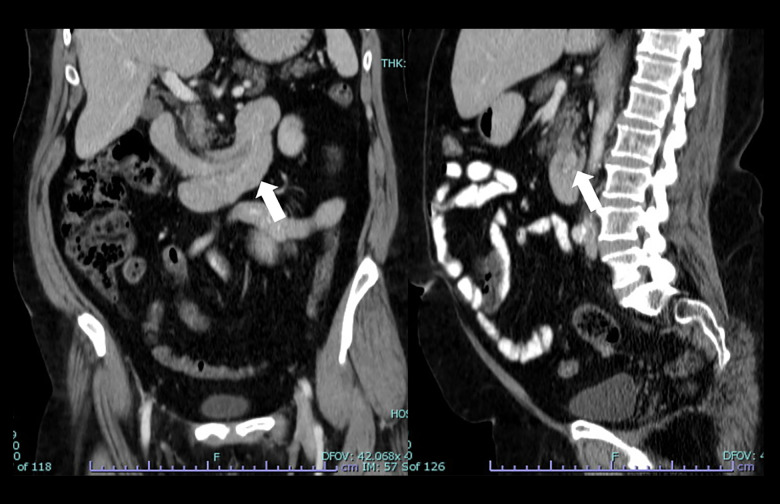

成人肠套叠(AI)是一种罕见的疾病,具有多种临床表现和管理挑战。尽管罕见,但了解其流行病学,临床特征和区分良恶性导点的预测因素对有效治疗至关重要。本研究旨在评估病理性人工智能患者的人口学和临床特征,并探讨与恶性导点相关的因素。材料与方法回顾性分析2014年1月1日至2024年1月1日诊断为AI的bb0 ~ 18岁患者的病历。根据肠套叠的部位和病因对患者进行分类。评估恶性导点的预测因素,包括年龄、性别、表现症状、位置和肠套叠大小。复习计算机断层扫描(CT)图像以确认诊断。排除短暂性小肠肠套叠及饲管相关肠套叠。结果10年内共发现病理性人工智能26例,男性占69.2%,平均年龄53.3岁。腹痛是最常见的症状(65.4%),诊断为肠梗阻的病例占23.1%。CT扫描是主要诊断方式(92.3%)。结肠肠套叠最为常见(53.8%),手术治疗较为常见(69.2%)。组织病理学检查显示大多数病例(57.7%)为良性铅点,以脂肪瘤和息肉最为常见。直肠出血与恶性导点显著相关(P=0.011)。结论人工智能具有多种临床特征。它主要影响结肠。直肠出血提示恶性铅点的可能性较大。多学科方法对于最佳的基于病例的管理至关重要。

BACKGROUND Adult intussusception (AI) is a rare condition with diverse clinical presentations and management challenges. Despite its rarity, understanding its epidemiology, clinical features, and predictive factors distinguishing benign and malignant lead points is crucial for effective management. This study aimed to assess the demographic and clinical characteristics of patients with pathological AI and examine factors associated with malignant lead points. MATERIAL AND METHODS Medical records of patients aged >18 years with diagnosis of AI between January 1, 2014, and January 1, 2024 were retrospectively analyzed. Patients were classified based on location and etiology of intussusception. Predictive factors for malignant lead points were assessed, including age, sex, presenting symptoms, location, and size of intussusception. Computed tomography (CT) scan images were reviewed for diagnosis confirmation. Transient small bowel intussusceptions and intussusceptions related to feeding tubes were excluded. RESULTS Twenty-six cases of pathological AI were identified over 10 years, with a male predominance (69.2%) and a mean age of 53.3 years. Abdominal pain was the most common presenting symptom (65.4%), with bowel obstruction diagnosed in 23.1% of cases. CT scans were the primary diagnostic modality (92.3%). Colocolic intussusceptions were most prevalent (53.8%), and surgical management was common (69.2%). Histopathological examination revealed benign lead points in the majority (57.7%) of cases, with lipomas and polyps being the most common. Bleeding per rectum was significantly associated with malignant lead points (P=0.011). CONCLUSIONS AI presents with diverse clinical features. It predominantly affects the colon. Bleeding per rectum indicates a higher likelihood of malignant lead points. A multidisciplinary approach is essential for optimal case-based management.